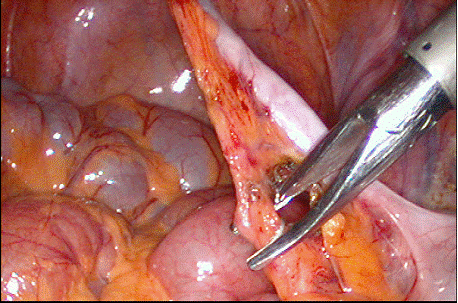

Se aplica o pensa atraumatica la nivelul varfului, dupa care se incepe disectia mezoapendicelui. Se pot folosi mai multe metode:

l daca mezoul este vizibil, nu este grasos sau inflamat si artera apendiculara se poate identifica, se creeaza o fereastra in mezou, deasupra ei si se aplica un clip pe vasele apendiculare, apoi se sectioneaza mezoapendicele; prin aceasta fereastra se poate introduce un fir neresorbabil pentru artera apendiculara, care se innoada intra - si extracorporeal; acest fir poate fi trecut si cu ajutorul unui ac;

Fig. 19 Aplicarea

clipurilor pe mezoapendice